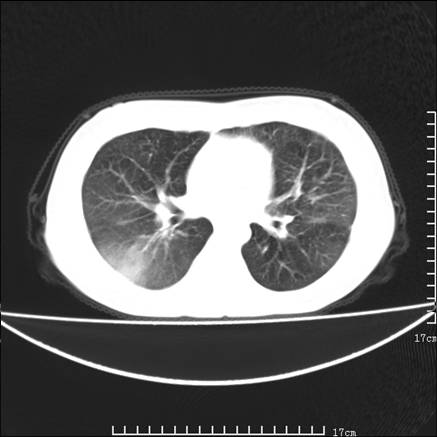

女,46岁,患胃溃疡多年,溃疡大小约1.0cm左右,后于5年前手术,病理为胃癌。主诉:半月前感冒后胸闷,气短,有咳嗽,无明显咳痰,无发热。偶有腰背部不适。

以下为高分辨扫描图像

正如caihe主任所言,影像表现结合临床病史应该支持肺癌性淋巴管炎;上肺大片边缘不清的渗出病变,多系感染所致,临床有感冒病史并咳嗽表现。肺癌性淋巴管炎临床一般无咳嗽、咳痰症状。

鉴别:

1、结节病,多位于肺的上中部和后部,呈向心性分布,造成近肺门区的支气管血管束周围间质和胸膜下间质增厚,小叶间隔增厚不明显,即使增厚也较为局限

2、尘肺,可以通过病史,肺外周为主的多发结节,胸膜假斑,聚合成的团块,间质纤维化等鉴别

3、肺水肿,肺水肿可以造成肺间质的增厚,为光滑的增厚且常为双侧对称性分布。